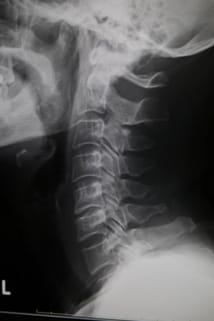

ストレートネックやスワンネック(図2)と俗に言われる、首の後ろの筋肉(僧帽筋)が弱く前側(胸鎖乳突筋)が張っていることが多いです。

頭部は約6kgの重さがあります。体の中心線から垂直の線上に第2頚椎の歯突起先端があり、それがやや後方に反っている形が正常(理にかなった形)。

スワンネックでは、長年の姿勢の癖で自分では感じませんが、頚椎の骨、中の脊髄や神経、頚動脈、頚静脈などに大変な負担がきています。その負担が慢性の頭痛、肩こり、首の痛み、めまいなどにつながります。この状態が続くとうつ病、自律神経失調症になり、回復不能となる事もあります。

第1椎間孔からは、耳介後部から後頭部、側頭部の頭皮部分、顔面への神経が出ています。変形性頚椎症により椎間孔が狭くなると、そこを通る神経が圧迫され、慢性的な痛み・しびれ、急性の痛み(後頭神経痛、首で生じると寝違え)が生じます。

頚椎牽引をすると、椎間孔を広げる作用があるといわれています。